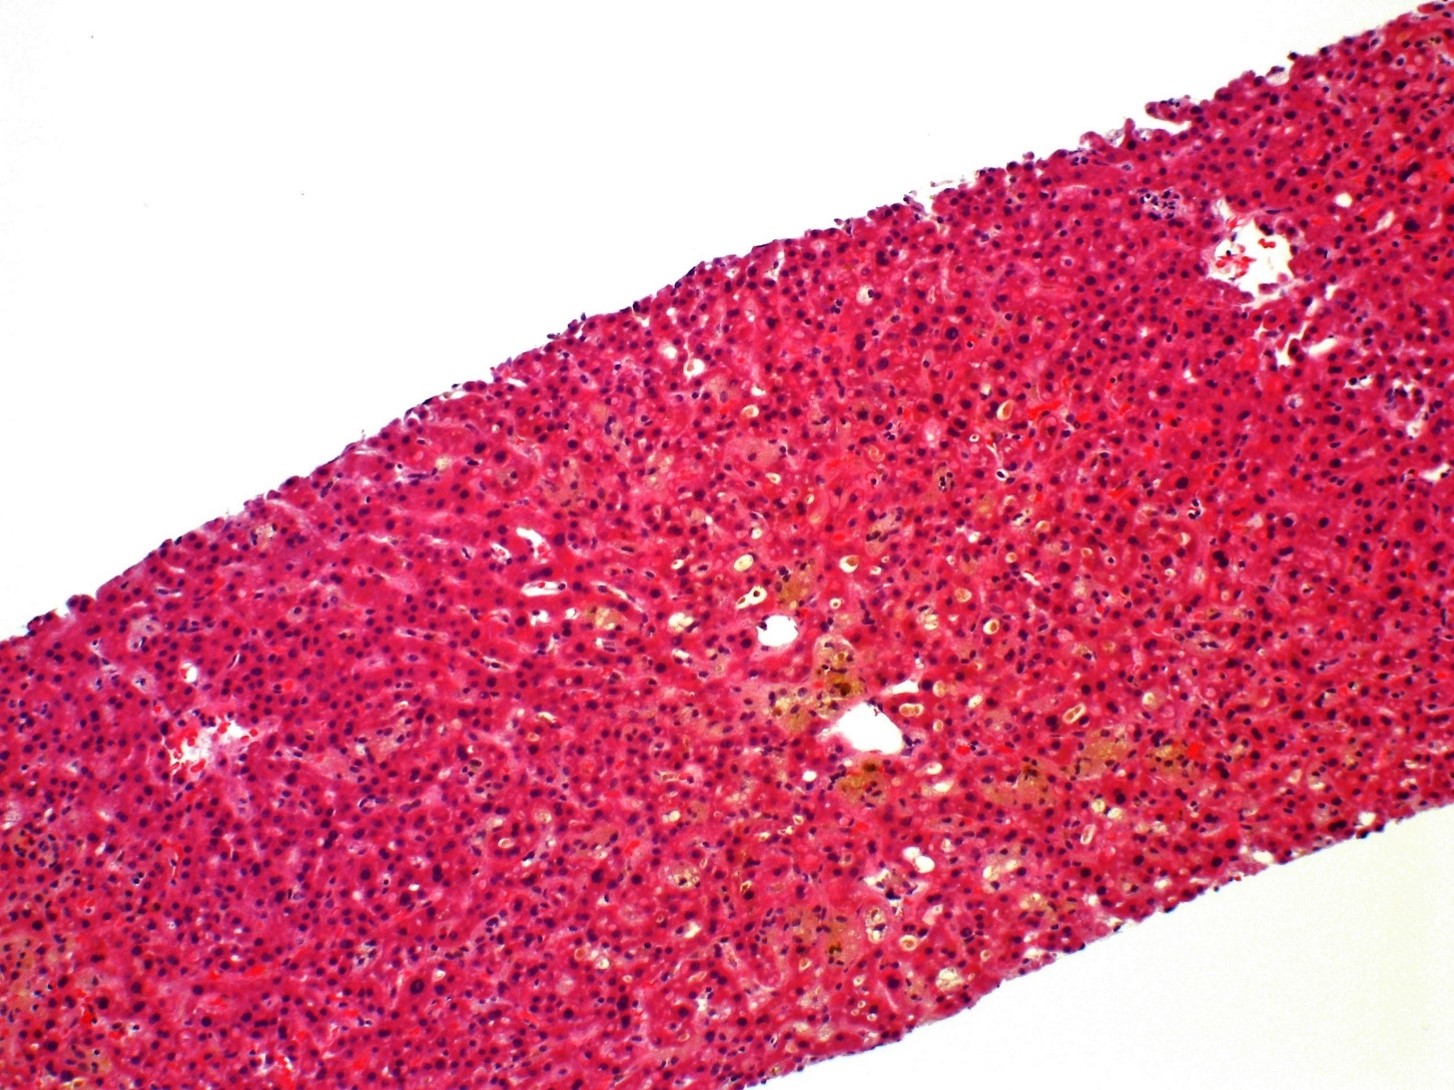

A 68 year old woman presents with a 5.8 cm adrenal mass identified incidentally...